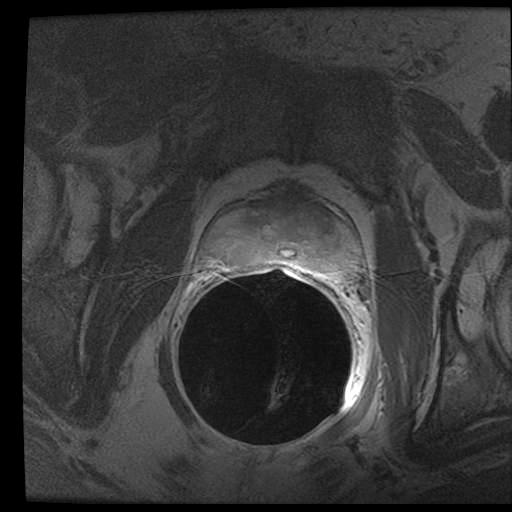

In the previous section, we simulated images in order to exploit “perfect segments”. In this section, we validate our approach using actual MR images of prostates. The image data from 15 patients were manually delineated by 5 oncologists.

The MR images used in this study were derived from an online database444http://prostatemrimagedatabase.com/. The database contains T2-weighted MR volume datasets, provided by Brigham and Women’s Hospital, the National Center for Image-guided Therapy, and Harvard Medical School. The images comprised T2-weighted MR images (T2W-MR) with endorectal coils. The pulse-sequence groups in the DICOM headers of most of the T2-weighted images were marked fast-spin echo (FSE), although some were marked as fast-relaxation fast-spin echo-accelerated (FRFSE-XL). The dataset contained images with slice thickness ranging from 2.5mm to 4.0mm, and varying contrast levels and signal-to-noise characteristics. All of the images were captured at a depth of 16 bits, and they varied in size from 256×\times256 to 512×\times512 pixels.

Sample images are depicted in Figure 6 (top row). Generally, one assumes that prostate segmentation is a relatively easy task. However, the variability of such segmentation remains considerable, and this is conspicuous in Figure 6 (bottom row).

Figure 6: Top: Sample MRI slices from different patients. Bottom: considerable variability among 5 oncologists.